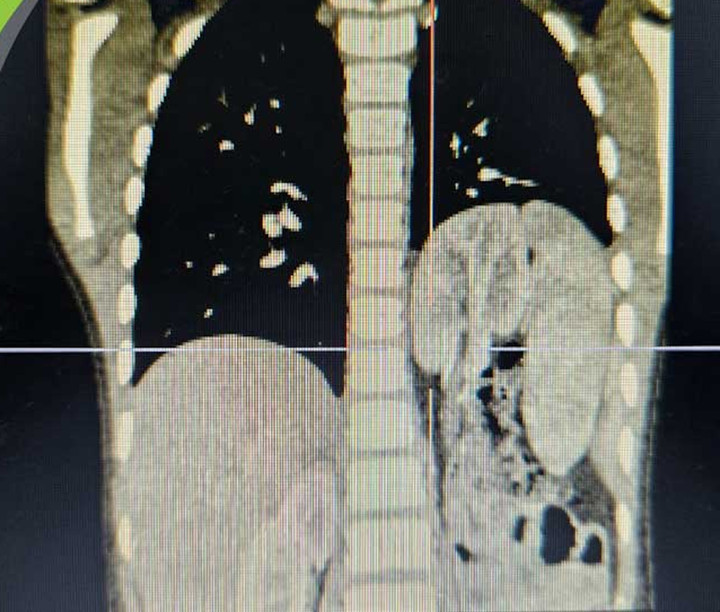

Hình ảnh chụp thoát vị hoành trái bẩm sinh với tạng thoát vị là lách, ruột non, đại tràng và kèm theo thận lạc chỗ trên lồng ngực của trẻ.

Phim chụp cắt lớp vi tính cho thấy các cơ quan thoát vị trở lại vị trí giải phẫu bình thường, cơ hoành liền tốt và phổi trái của bé nở đều. Chức năng thận trái sau khi trở về ổ bụng cũng được đánh giá không có bất thường. Bệnh nhi hồi phục ổn định và được xuất viện sau 7 ngày.